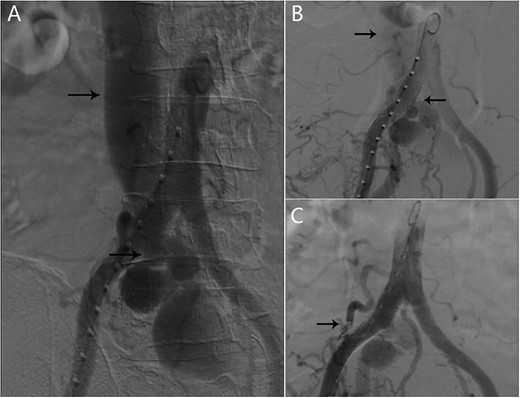

He had multiple hospital admissions with left lower limb edema and heart failure. He was diagnosed with deep vein thrombosis and pulmonary hypertension in the local hospital. On admission, clinical examination revealed bilateral basal rales in the lungs and abdominal bruit. The blood biochemical indexes were NT-proBNP 1075 pg/ml, and other biochemical indexes were within the normal range. Echocardiography demonstrated showed a severely dilated right ventricle. Chest X-ray revealed lung infection and pulmonary hypertension. Computed tomography angiography (CTA) showed there was an AVF between the right internal iliac artery and the left common iliac vein and dilated tortuous veins in the left lower limb (Fig. 1).

CTA showing AVF between the right internal iliac artery and the left common iliac vein. (A) The left common iliac vein and dilated tortuous veins in the left lower limb; (B, C) An AVF (black arrow) between the right internal iliac artery and the left common iliac vein.